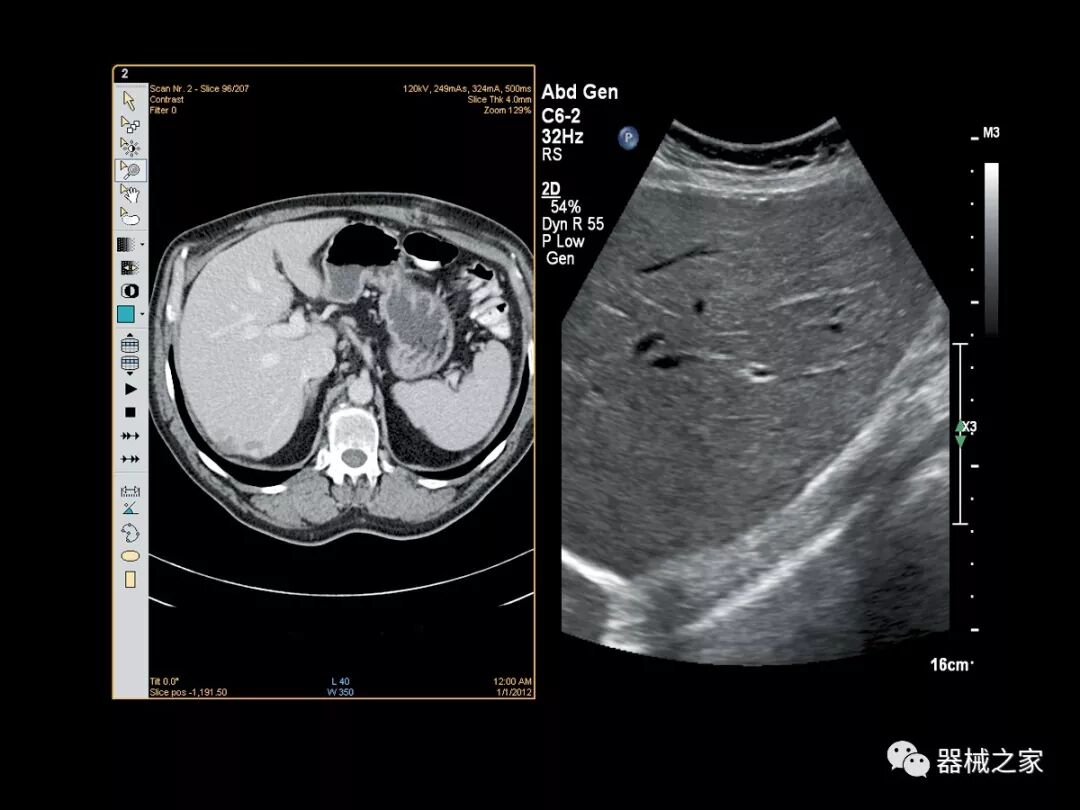

Baptist Health South Florida成为去年秋天西门子医疗保健公司Acuson Sequoia的首个商业安装网站。该系统将有助于增强胃肠病学,初级保健和减肥专业的成像能力。Sequoia可实现高分辨率成像,自动适应患者的体型和个人身体特征,有助于更加自信的诊断。它适应患者的组织密度,刚度和超声波束吸收的生物声学变化。这使得系统可以穿透高达40厘米而不会因衰减回波信号而导致图像质量下降。